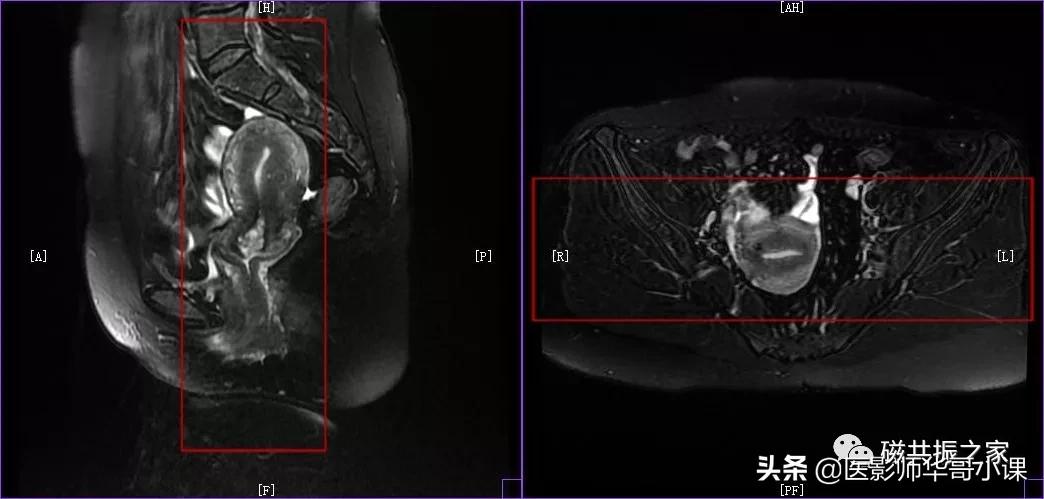

在横轴位和冠状位上定位。在横轴位上找到显示子宫体最大的层面,使定位线垂直于当前子宫内膜长轴,在冠状位上调整角度使定位线平行于子宫全长长轴(平行于子宫颈和子宫底中点的连线);如是宫颈病变,应以宫颈管为基准定位。左右扫描范围包括整个子宫,需包括整个病变范围。

在横轴位和矢状位上定位,在矢状位上找到显示子宫全长最好的层面,如需了解宫颈病变,使定位线平行于宫颈管长轴(图A),如需了解子宫内膜病变,使定位线平行于子宫内膜长轴。在横轴位上找到显示子宫最大的层面,使定位线平行于当前子宫内膜长轴,扫描范围包括整个子宫及两侧附件,需包括整个病变范围。